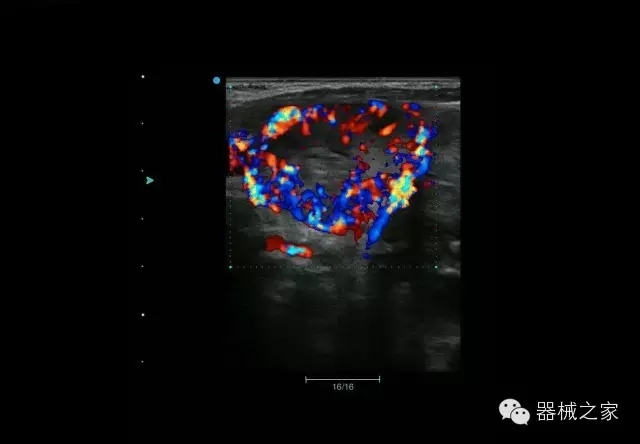

臨床圖片賞析

睪丸低速血流

臍帶血流

頸動脈頻譜